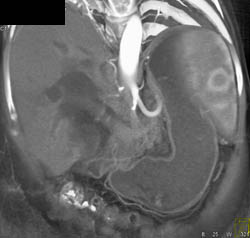

Hepatic Artery Pseudoaneurysm